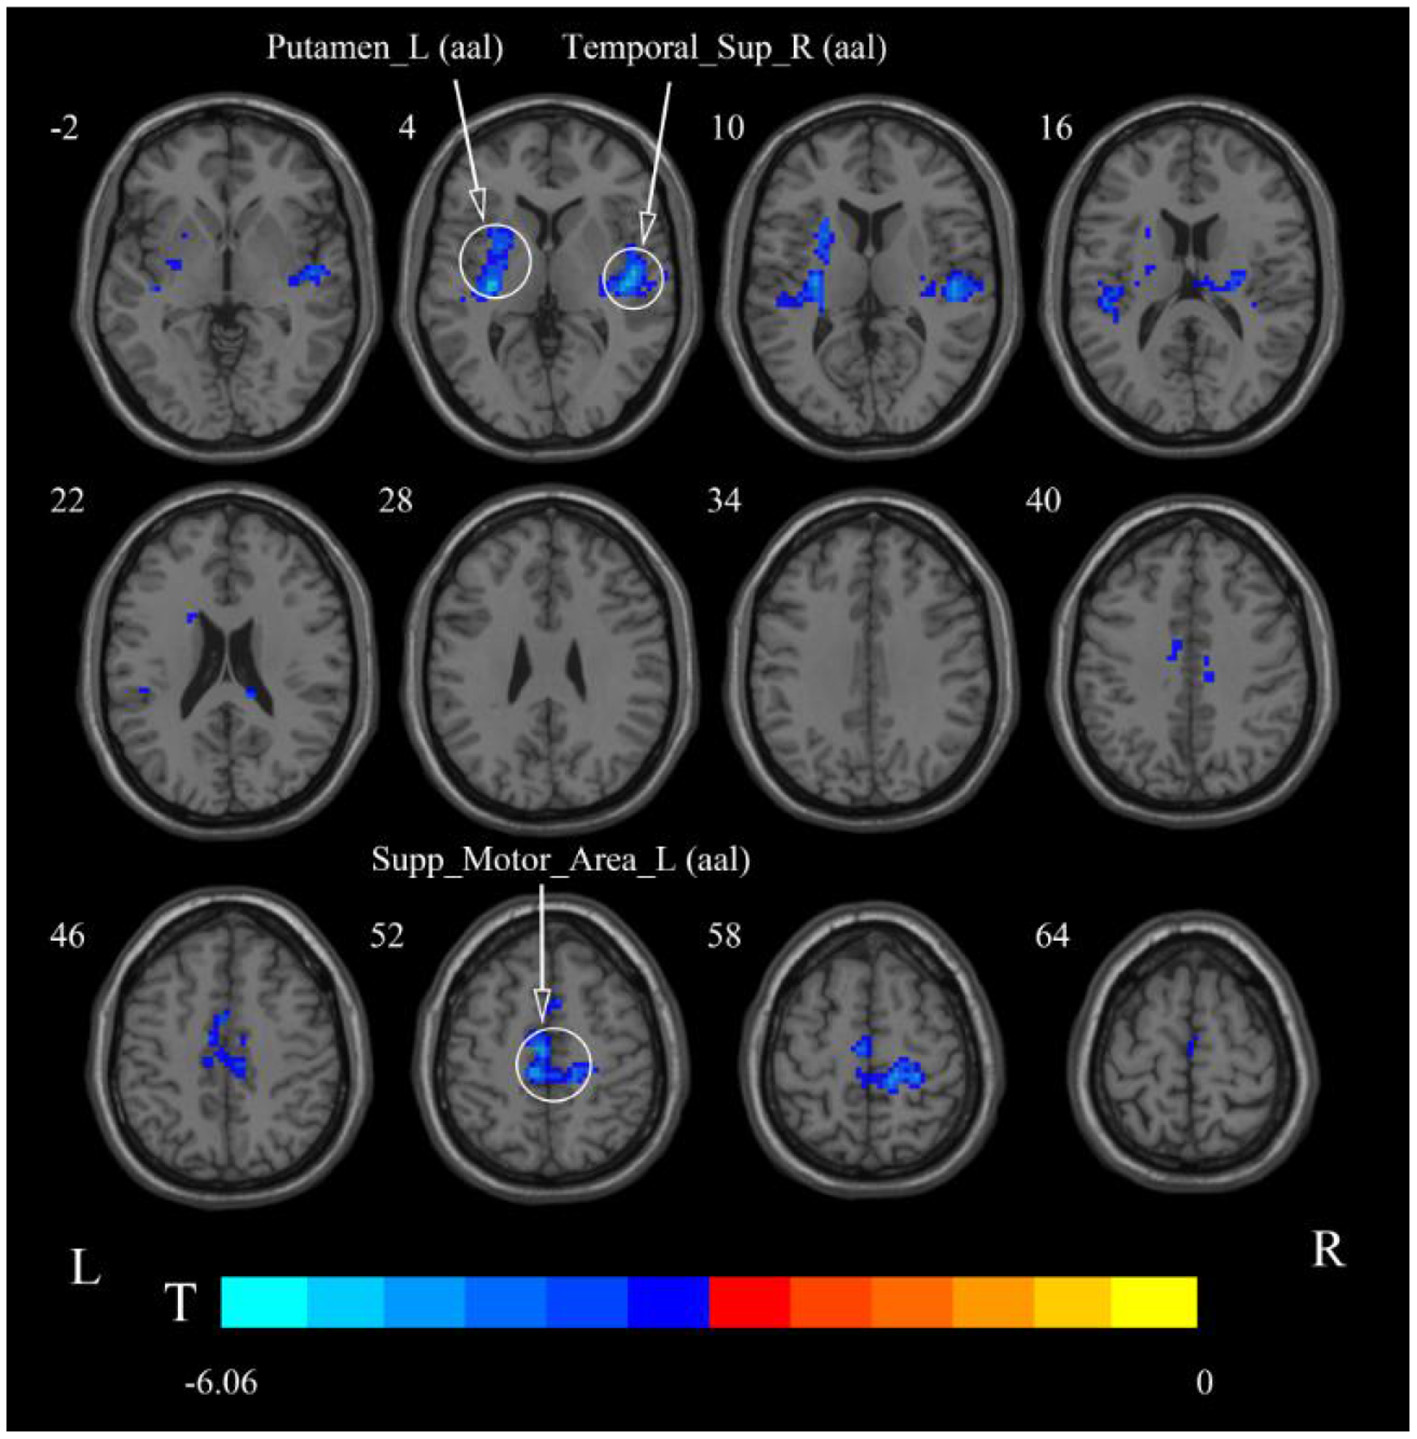

After cerebellar stimulation, in the classical frequency band we found significantly decreased ReHo at the left insula, right temporal lobe, and corpus callosum (p < 0.05; Figure 6 and Table 2). In addition, a decrease in ReHo was also found at the left insula and corpus callosum in the slow-4 band and at the right temporal lobe, left putamen, and left motor accessory area in the slow-5 band (p < 0.05; Figures 7, 8 and Table 2).

Figure 8. Statistical maps showing ReHo change pre- and post-rTMS in the slow-5 band. Cool colors showing ReHo decreased after rTMS p < 0.05.